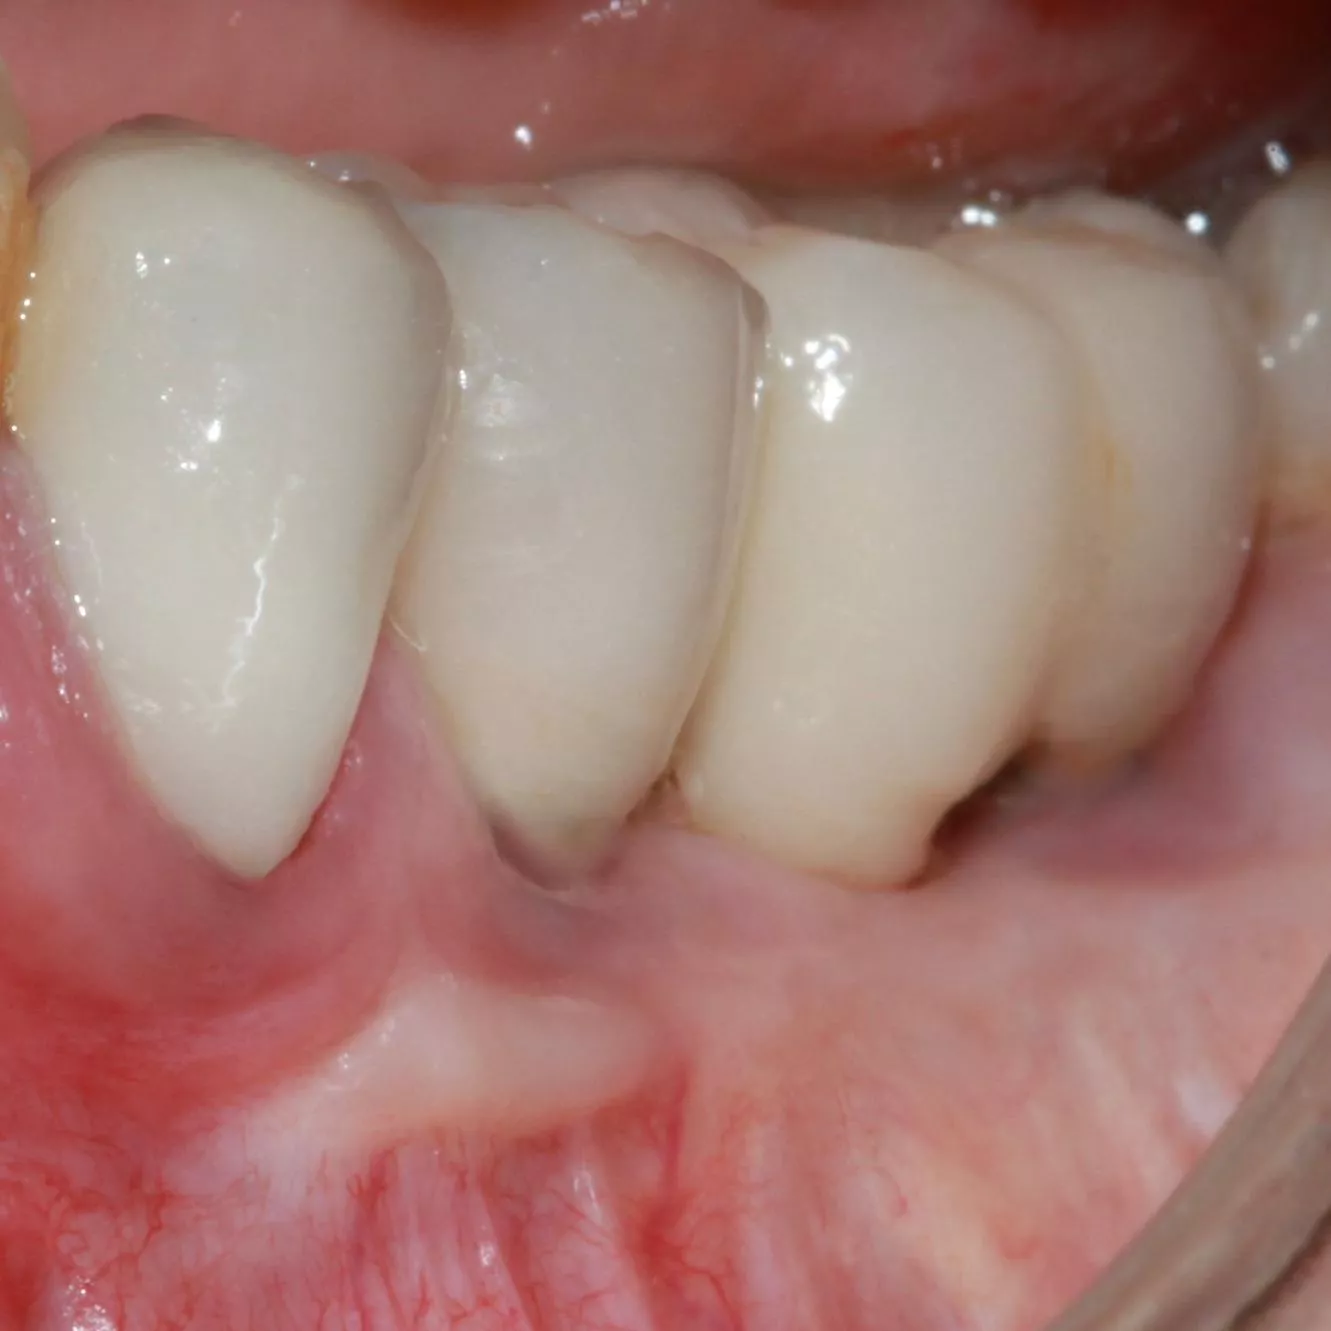

8. 10 days later, satisfactory healing of the mucogingival procedure.

10. Clinical situation 2 years later with the crowns screwed onto the MU abutments (Dr S. Abid, Nice).